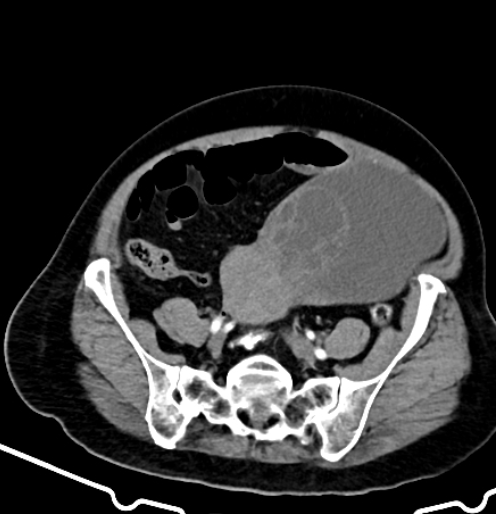

Mucinous Cystadenoma

• Multiloculated

• Thin walled with septa

• Simple and/or complex fluid